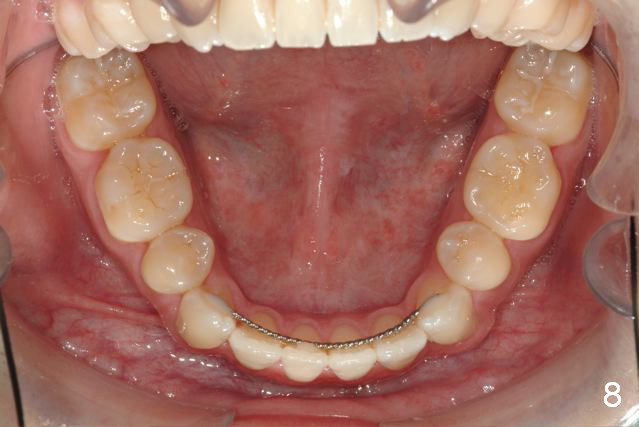

Initial information was obtained on 02/26/2014 (Fig.1-10). Anterior edge-to-edge and Posterior Open Bite (Fig.4 *): unfavorable differential Class III growth after orthodontics as a child.